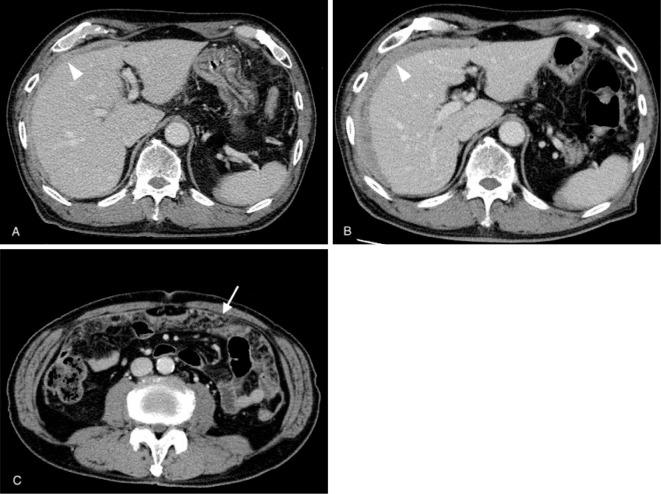

Malignant peritoneal mesothelioma (MPM) is a rare malignant tumor with peritoneal thickening. Tuberculous peritonitis also shows peritoneal thickening, so differentiating between the two is important but difficult if latent tuberculosis infection (LTBI) is present. We herein report a patient with MPM and LTBI. A 79-year-old man was diagnosed with peritoneal thickening on computed tomography. Interferon gamma release assay (IGRA) results were positive, suggesting tuberculous peritonitis. He underwent a laparoscopic omental biopsy and was diagnosed with MPM, which can occur together with LTBI. If peritoneal thickening is observed, an IGRA should be performed early, and the possibility of LTBI should be considered.

恶性腹膜间皮瘤(MPM)是一种伴有腹膜增厚的罕见恶性肿瘤。结核性腹膜炎也表现为腹膜增厚,因此区分两者很重要,但如果存在潜伏性结核感染(LTBI)则很难区分。我们在此报告一例患有MPM和LTBI的患者。一名79岁男性在计算机断层扫描中被诊断为腹膜增厚。干扰素γ释放试验(IGRA)结果呈阳性,提示结核性腹膜炎。他接受了腹腔镜网膜活检,被诊断为MPM,MPM可与LTBI同时发生。如果观察到腹膜增厚,应尽早进行IGRA检查,并考虑LTBI的可能性。